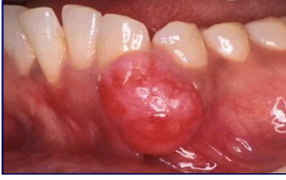

19

Q

what is this

A

pregnancy epulis